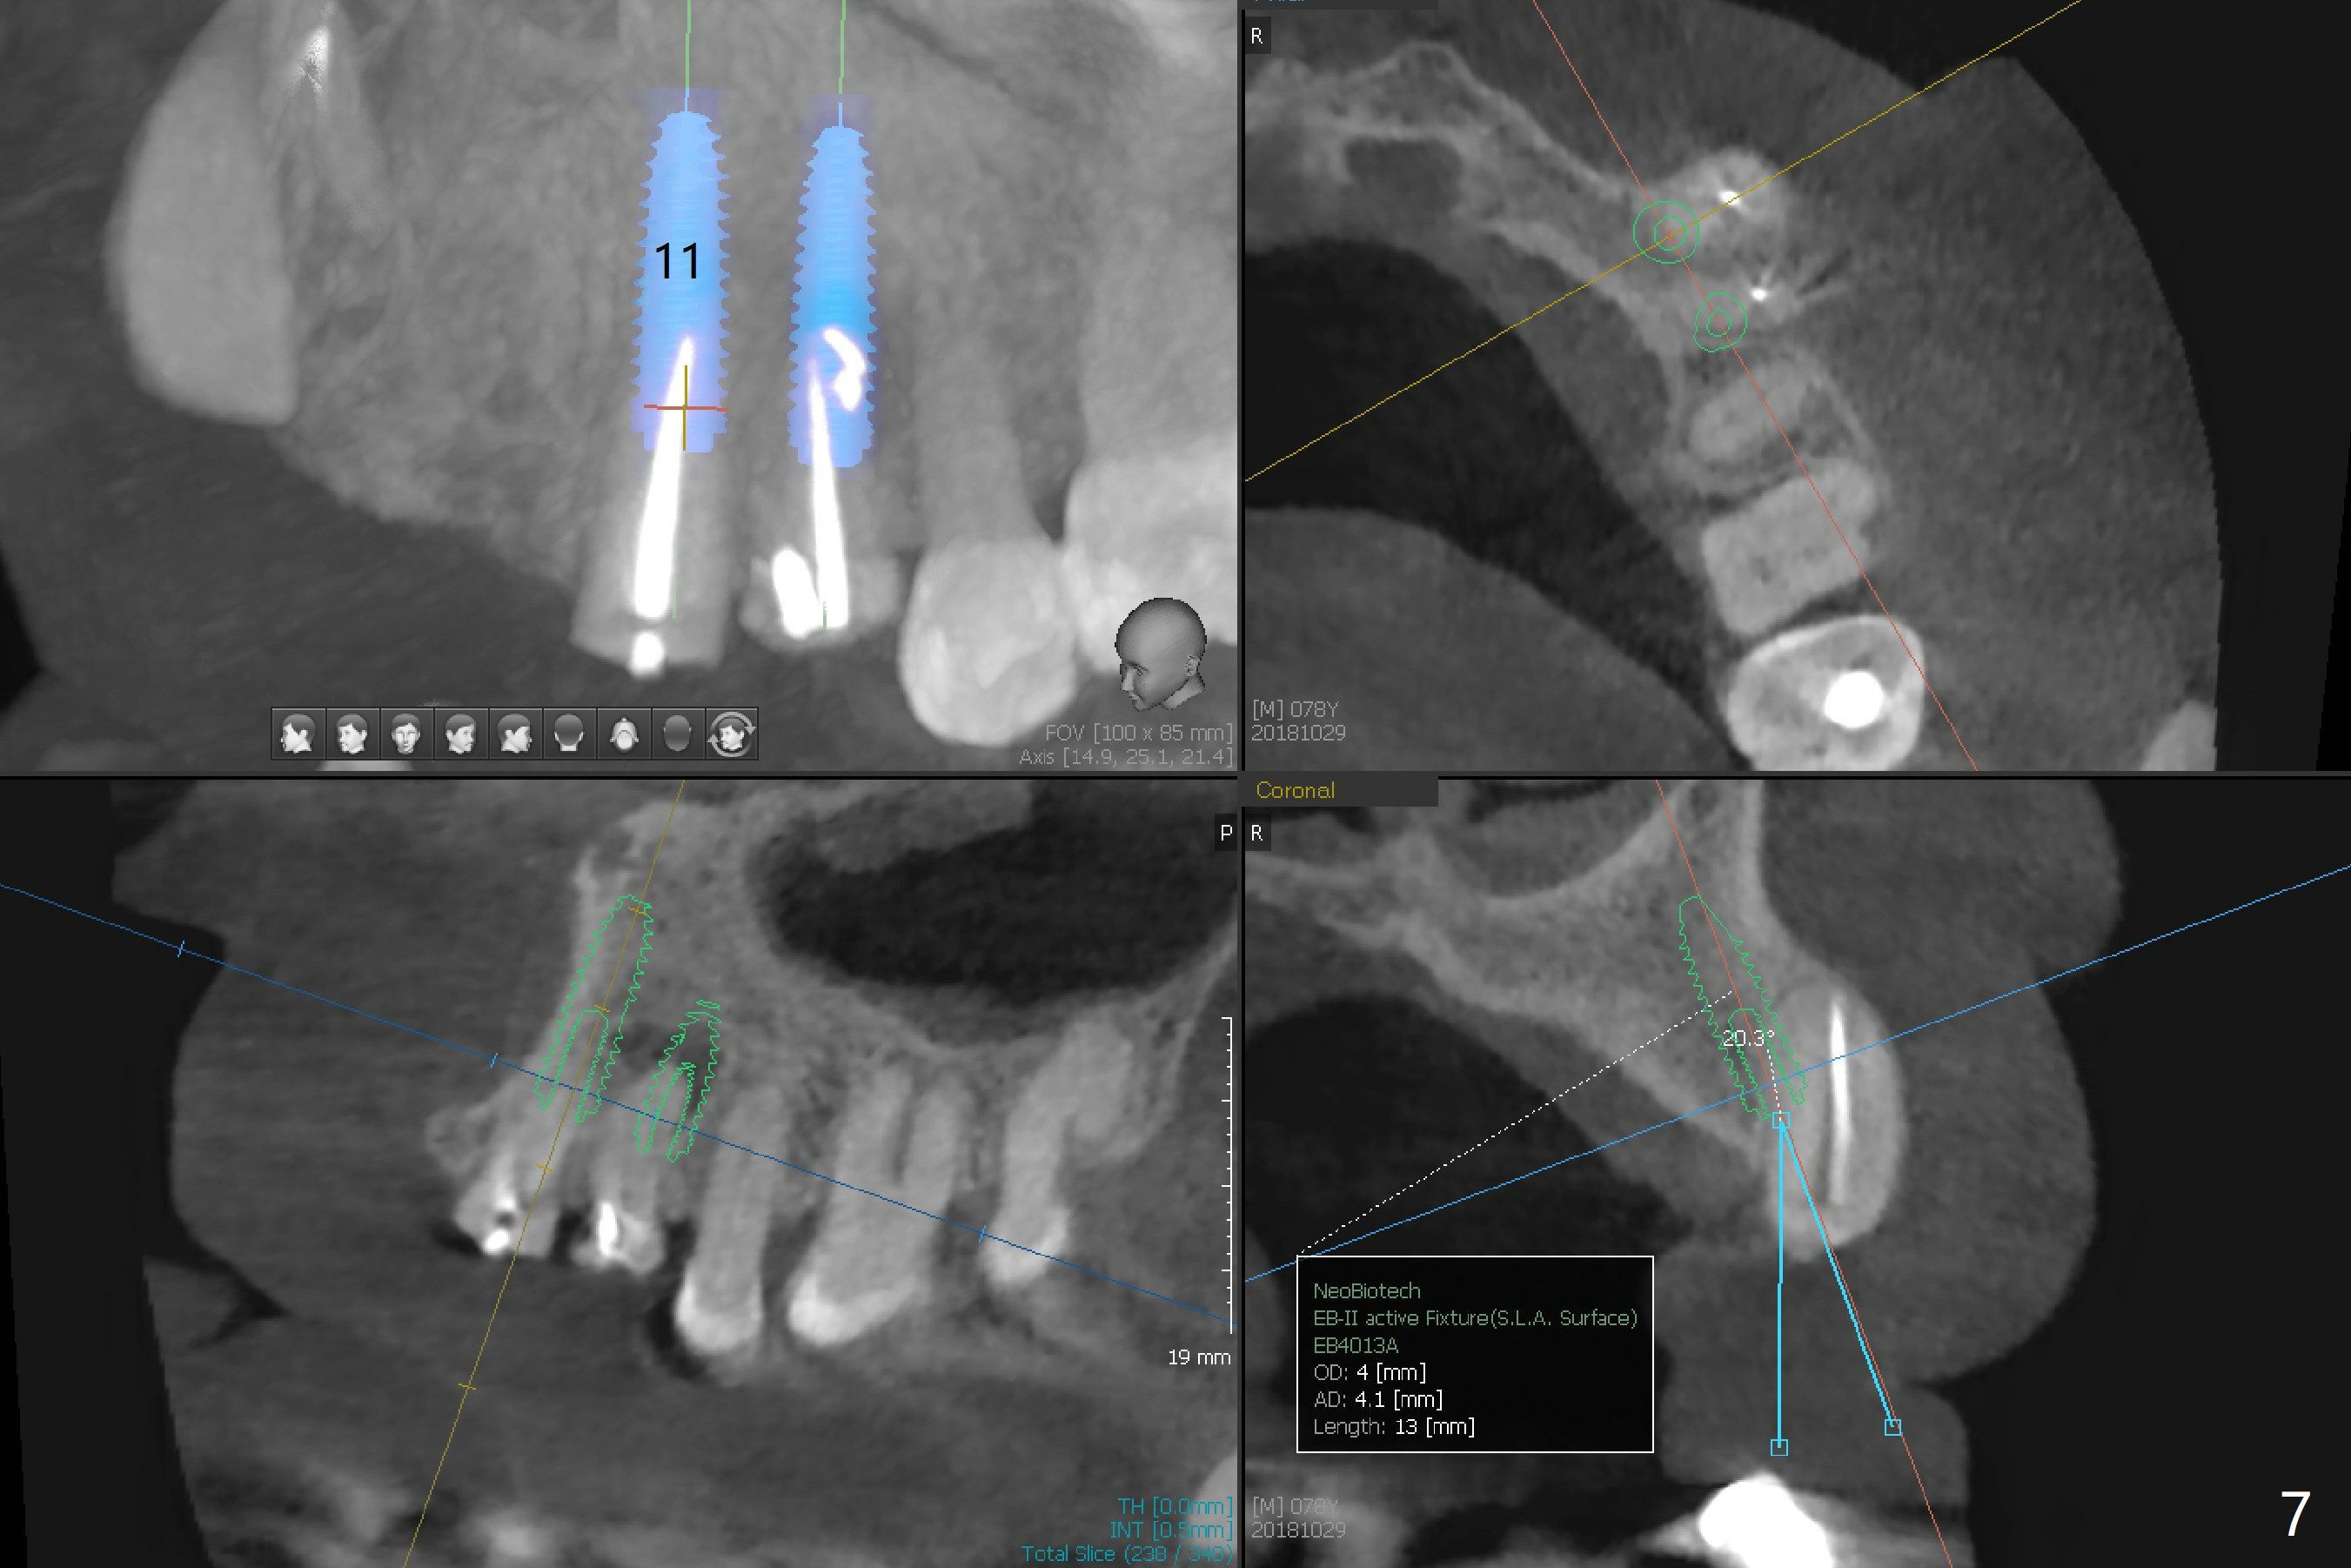

A 78-year-old man's 8 unit FPD dislodges (#5-12, Fig.1). Three of 4 abutments seem to be non-salvageable (#6,11,12 fractured equigingival, extraction, immediate implants). For restoration, implant will be placed at #8 and 9 as well. Implant FPDs will be fabricated at #6-8 and 9-11 (Fig.2) with #5 (with build up or prefabricated post) and 12 single unit crowns to better withstand deep overbite and overjet. After discussion with lab, a major change will be implants to be placed at #7 and 10 instead of #8 and 9 (narrow ridge). The implant at #7 will be a 1-piece (3 mm in diameter), whereas the rest 2-piece (3.5 mm). The abutment of IS 1-piece implant is 10 mm in length, while that of DIO's 5 mm. The former will be used if the vertical space is sufficient.